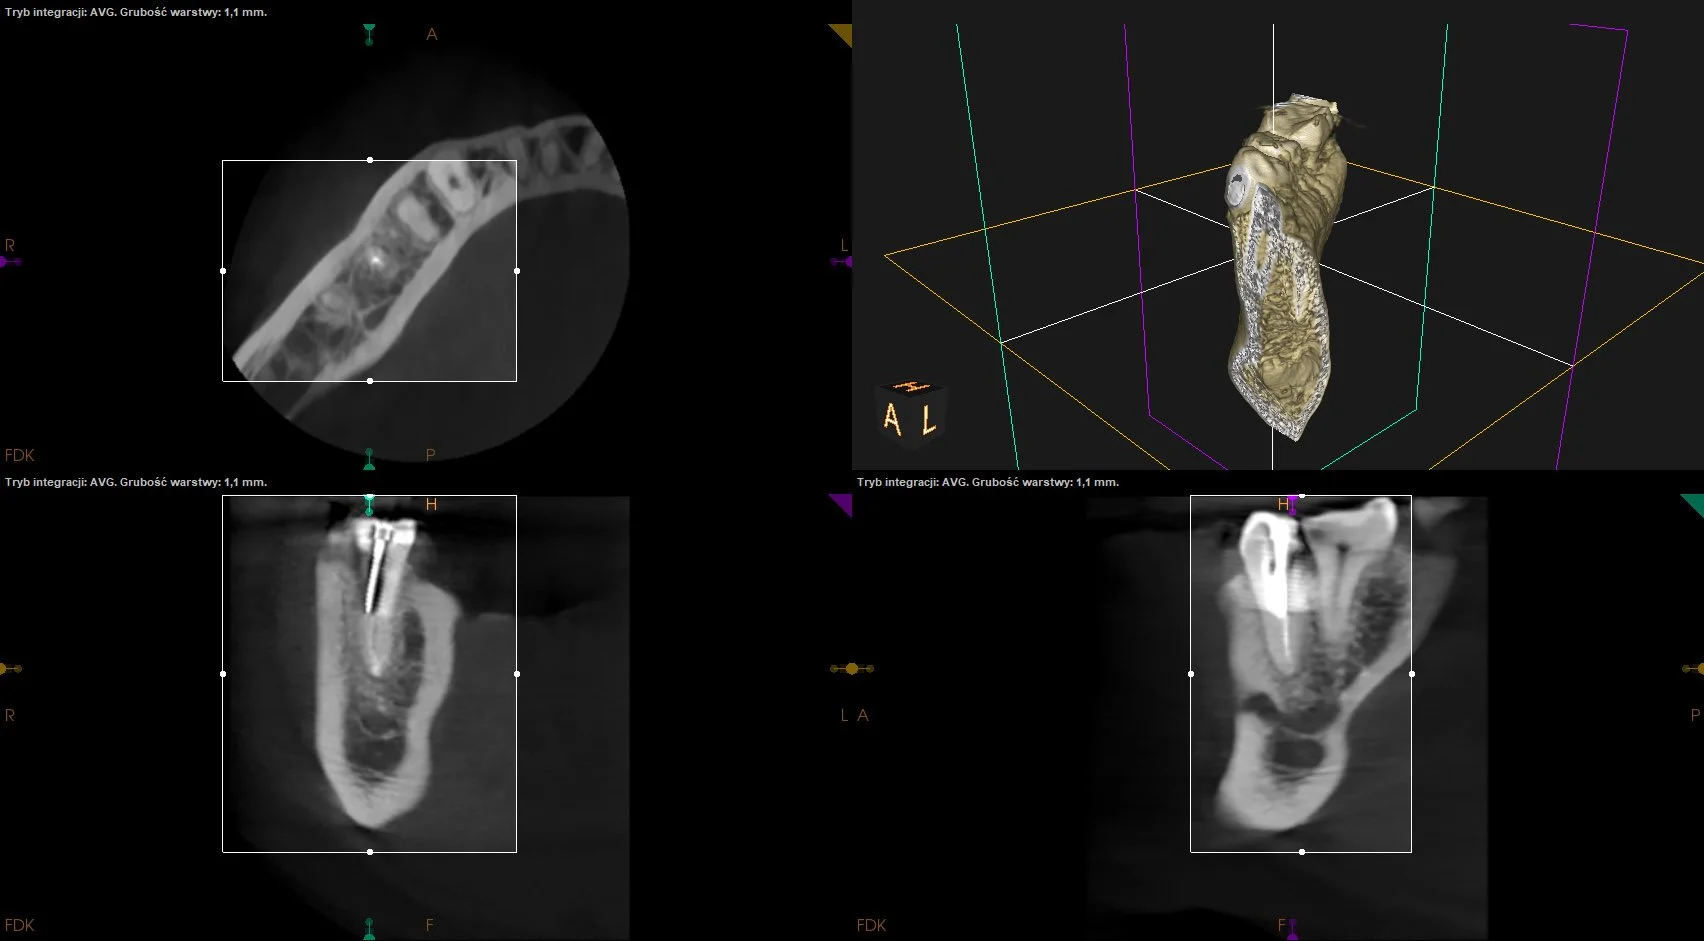

Usunięcie ankera zacementowanego na cement kompozytowy oraz reendo d.45 wraz z wykonaniem odbudowy adhezyjnej.

CASE STUDY X